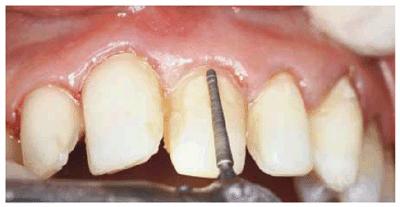

gingival discrepancy, then surgical intervention may not be necessary (Figures 24-2A 24-2B 24-2C, and 24-2D

Figure 24-2A: This patient was dissatisfied with her crowded anterior teeth. Note how the gingival height differs between the central and lateral incisors.

Figure 24-2B: The dissimilar gingival heights did not bother the patient because her natural smile line concealed these irregularities.

Figure

24-2C: After a slight reproportioning of the six anterior teeth, direct

composite resin was placed and contoured (6-mm ET [Brasseler,

Figure 24-2D: The final result shows improved proportion in tooth size and form.